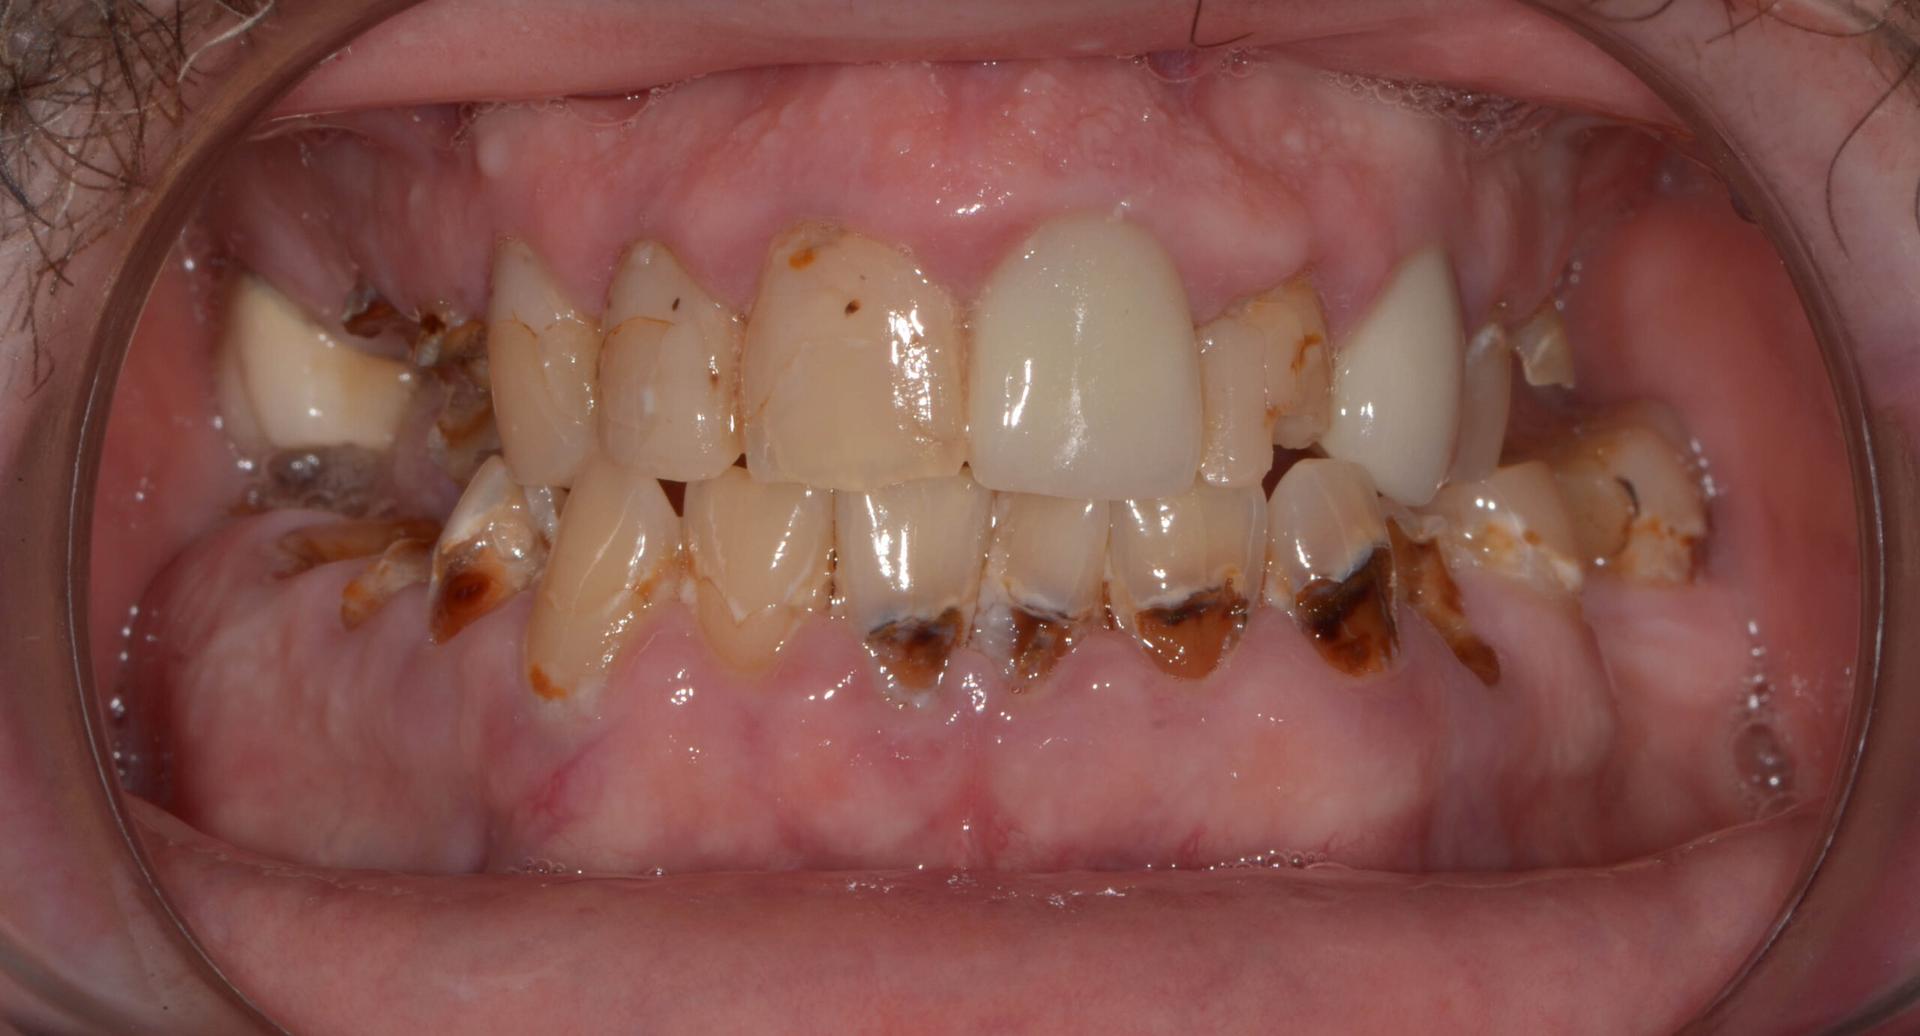

Rising Tooth Decay Among School Children Alarms Health Experts in Ghana

Health experts in Ghana are raising concerns over a noticeable increase in tooth decay among school-aged children, warning that poor oral hygiene and changing dietary habits are contributing to a growing public health issue. Reports indicate that dental decay is now affecting a significant number of pupils, highlighting the urgent need for preventive care and awareness.

Dental decay, commonly called cavities, occurs when acids produced by bacteria in the mouth erode the enamel — the hard outer layer of the tooth. These acids are formed when bacteria feed on sugars found in food and drinks. Frequent consumption of sugary snacks and beverages, combined with irregular or ineffective tooth brushing, makes children particularly vulnerable to cavities.

Experts point to several factors driving the increase in tooth decay among children. Chief among them is the growing consumption of sugary foods, soft drinks, and fruit juices. Many children snack frequently between meals without proper oral hygiene, allowing plaque — a sticky film of bacteria — to accumulate and cause enamel erosion.

In addition to diet and fluoride use, limited access to regular dental check-ups exacerbates the problem. Without routine dental visits, early signs of cavities often go undetected, leading to more serious oral health issues. Many parents only take their children to a dentist when there is pain or visible decay, missing the opportunity for early intervention.

The impact of untreated tooth decay extends beyond oral pain. Children with cavities often struggle to eat, sleep, or concentrate in school, which can affect their overall development and academic performance. Health experts stress that prevention is far more effective and less costly than treatment for advanced dental problems.